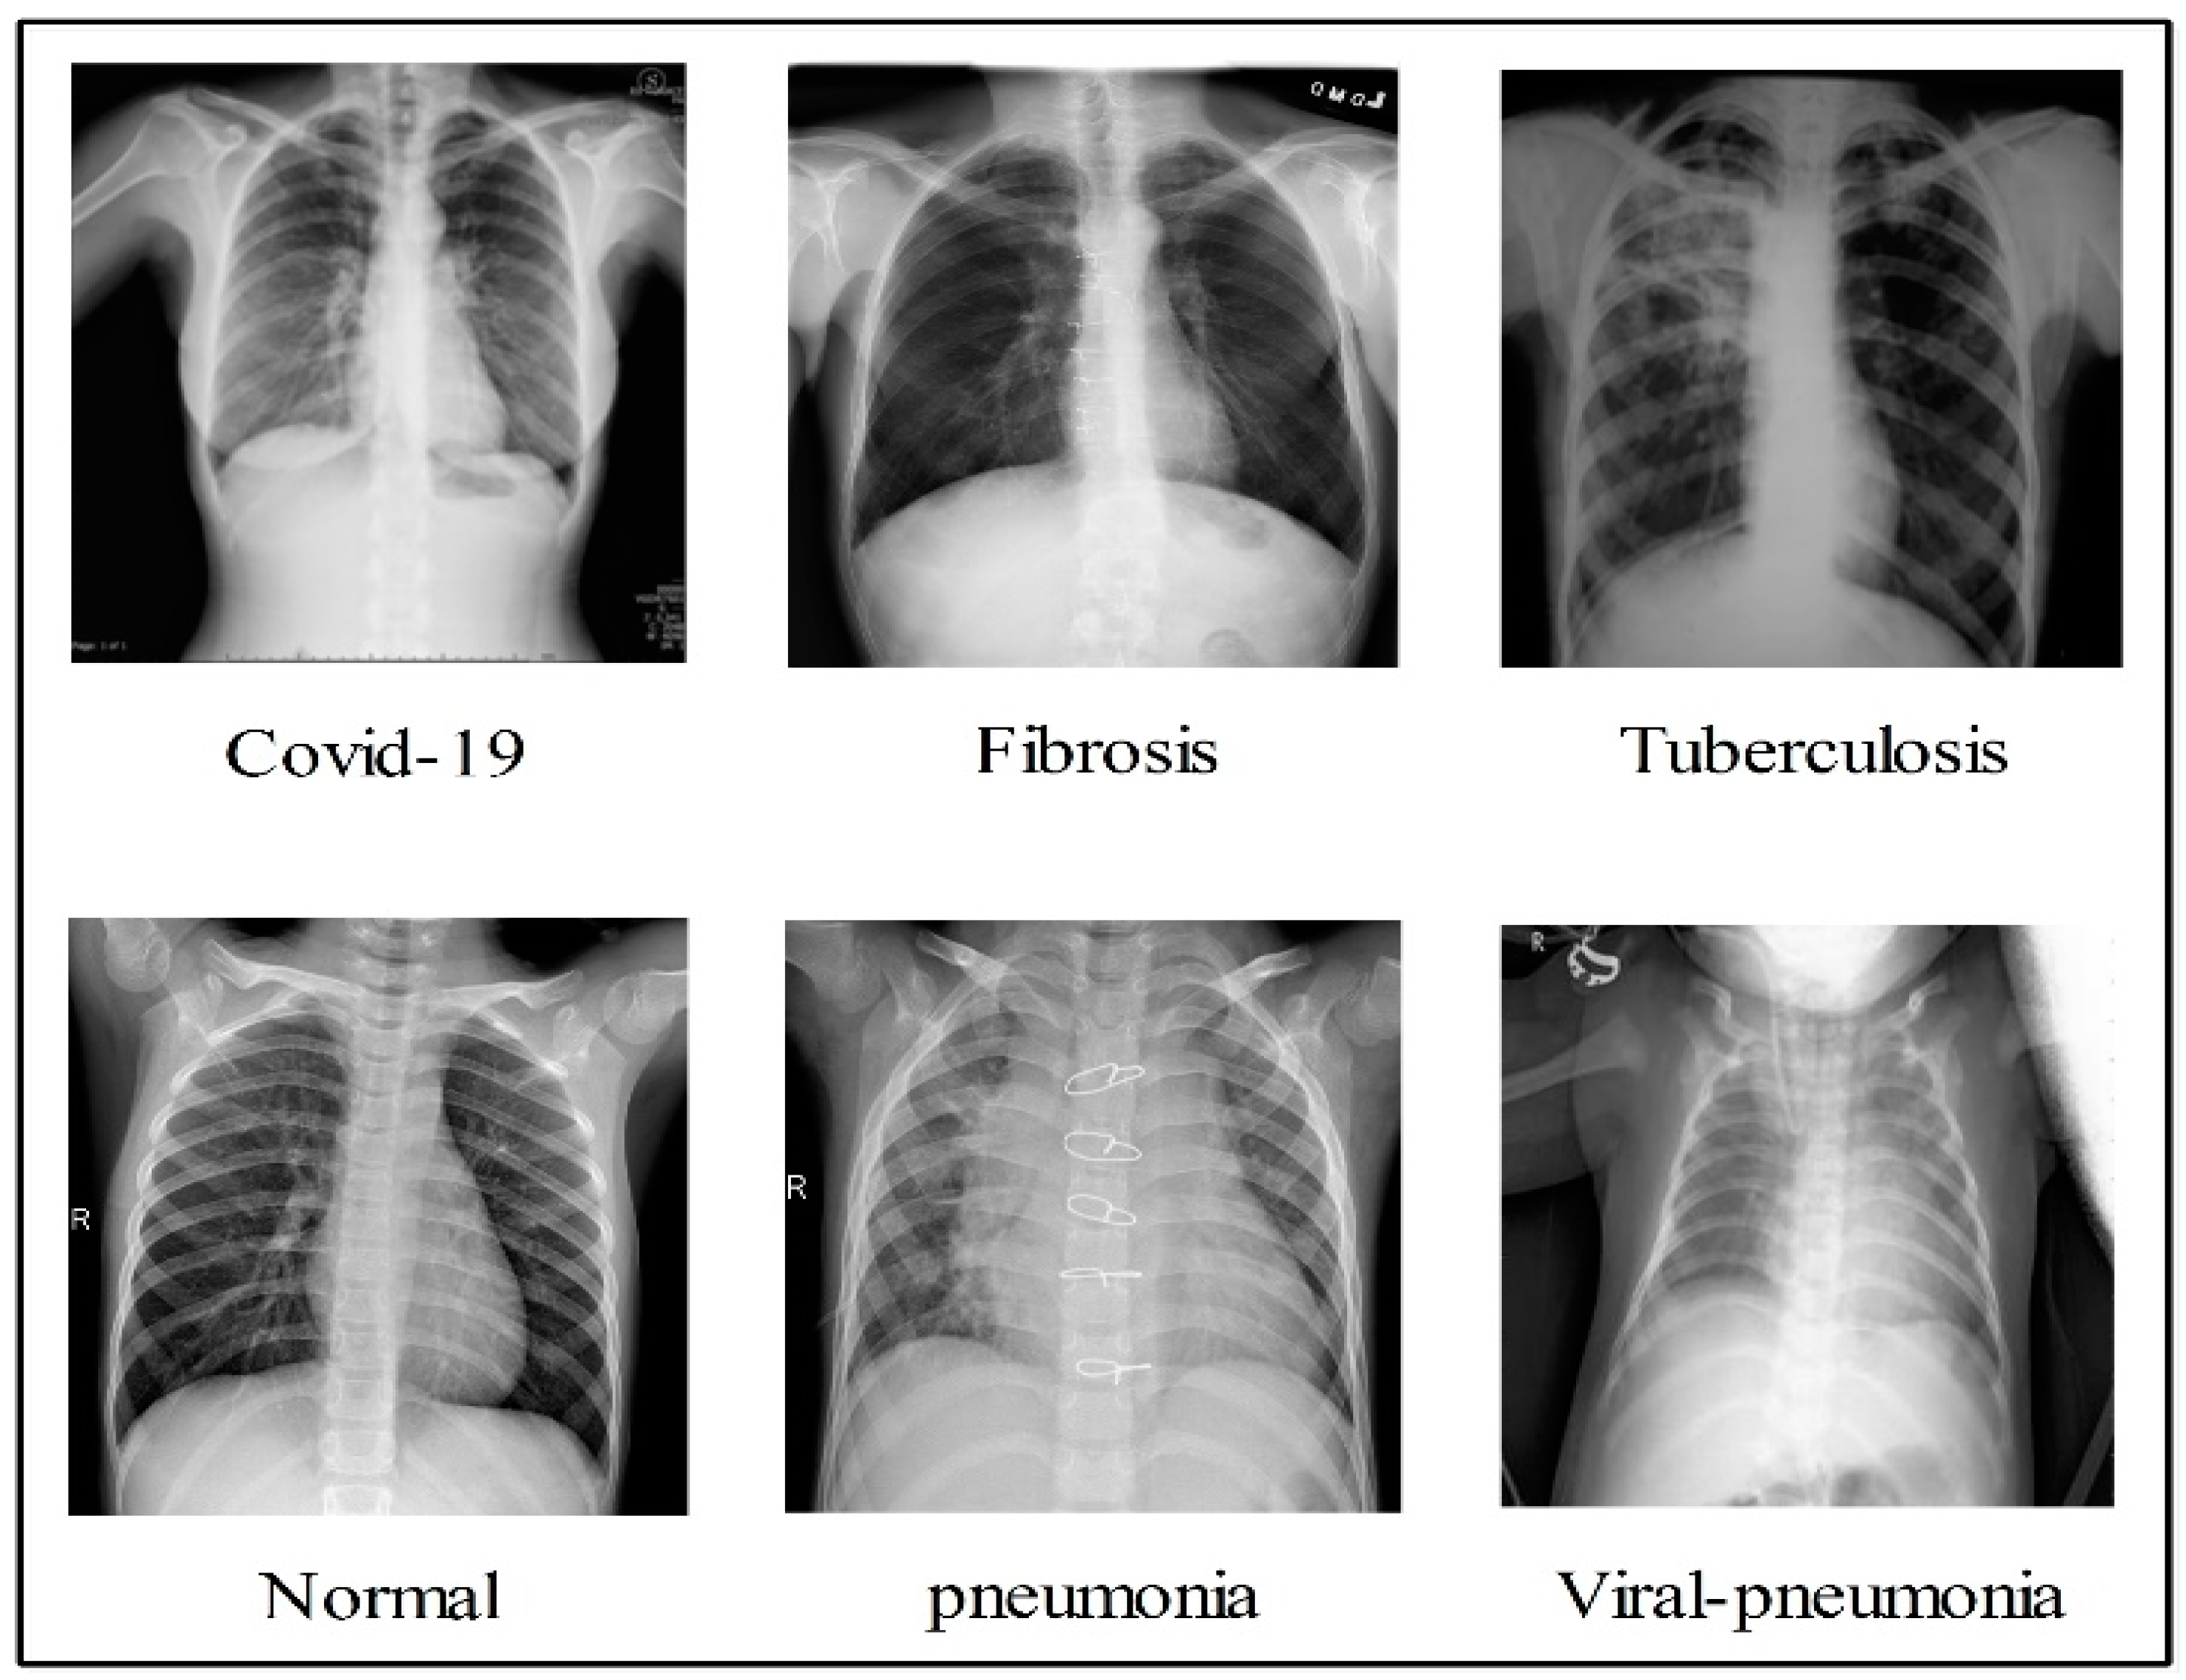

In the summary, the authors in the literature used pre-trained models with transfer learning concepts for COVID-19 classification. Few of them focused on the binary class problem, and many of them considered the multiclass problem. The deep models were trained using static hyperparameters, such as learning rate, depth section momentum, and the number of epochs. In addition, the authors selected a relatively small number of datasets for the training process. There are several challenges in effectively classifying COVID-19 using standard chest X-rays. Individuals with COVID-19 may have radiological imaging that resembles that of patients with bacterial or viral pneumonia, most notably those caused by SARS and MERS. As a result, the ability to correctly diagnose diseases by examining medical imagery has become a critical challenge. The first issue is the classification of multiple classifications, including COVID-19, viral pneumonia, lung opacity, TB, fibrosis patterns, and normal images. This is a challenge, since there are so many different types of lung diseases. These images are shown quite well in Figure 2. This figure illustrates that there is a high degree of resemblance between each image, which means that there is a chance that an incorrect classification will be made. The second challenge is the removal of redundant and useless information, which lowers the accuracy of classification, while simultaneously increasing computation time.

Figure 2.

Sample images of each class infections.

In this work, we used five publically available datasets for the experimental process. The selected datasets are Chest X-ray (https://www.kaggle.com/datasets/prashant268/chest-xray-covid19-pneumonia (accessed on 27 November 2022)), COVID-19 Patients Lungs X-ray Images (https://www.kaggle.com/datasets/nabeelsajid917/covid-19-x-ray-10000-images (accessed on 27 November 2022)), COVID-19 Lung CT Scans (https://www.kaggle.com/datasets/luisblanche/covidct (accessed on 27 November 2022)), COVID-19 Detection (https://www.kaggle.com/datasets/donjon00/covid19-detection (accessed on 27 November 2022)), and COVID-19 Image dataset (https://www.kaggle.com/datasets/pranavraikokte/covid19-image-dataset (accessed on 27 November 2022)). The three classes in the Chest X-ray dataset include COVID-19, normal, and pneumonia. COVID-19 Patients Lungs X-ray Images dataset has two classes, which are COVID-19 and normal. The COVID-19 Lung CT Scans dataset consists of CT images. It has two classes: COVID-19 and non-COVID-19. COVID-19, normal, pneumonia, tuberculosis, and fibrosis are the five classes in the COVID-19 Detection dataset. In the COVID-19 Image dataset, three classes exist: COVID-19, normal, and viral pneumonia. A few sample images are shown in Figure 2. The images in these datasets were not enough for training, as is shown in Table 1 (training images column). Therefore, we performed data augmentation based on three operations: flip right, flip left, and rotate 90 degrees. These operations were performed for each class for all five selected datasets. The number of target images for each class included 4000; therefore, we performed these operations multiple times. The details of the datasets are shown in Table 1. Moreover, these operations are visually shown in Figure 3.